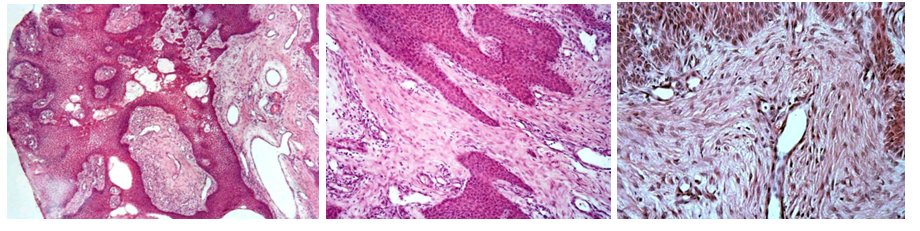

237. Fibropapilloma (Papillomatosis in cattle)

Description: Proliferation of fibrous tissue is as great or greater than that of epithelial tissue. Fibrous tissue forms whorls of fibers and has plumb, stippled nuclei with few mitotic figures. Epithelial rete pegs penetrate deep into fibrous moiety. On the surface of epidermis there is excessive hyperkeratosis and down also parakeratosis. Epidermal cells under hyperkeratosis or parakeratosis undergo dystrophy, and cytoplasm contain smaller and larger eosinophilic clumps.

Etiology: Virus-induced tumor commonly found on vulva and glans penis of younger animals. It is usually caused as a reaction to bovine verrucae virus. They can also be found in the periocular region and on the ventral part of the abdomen.

Pathogenesis: Virus infecting the keratinized bovine skin provokes the formation of the papilloma of relatively scant connective tissue core and abundant epidermal overgrowth. The result is one or multiple wart-like growths.